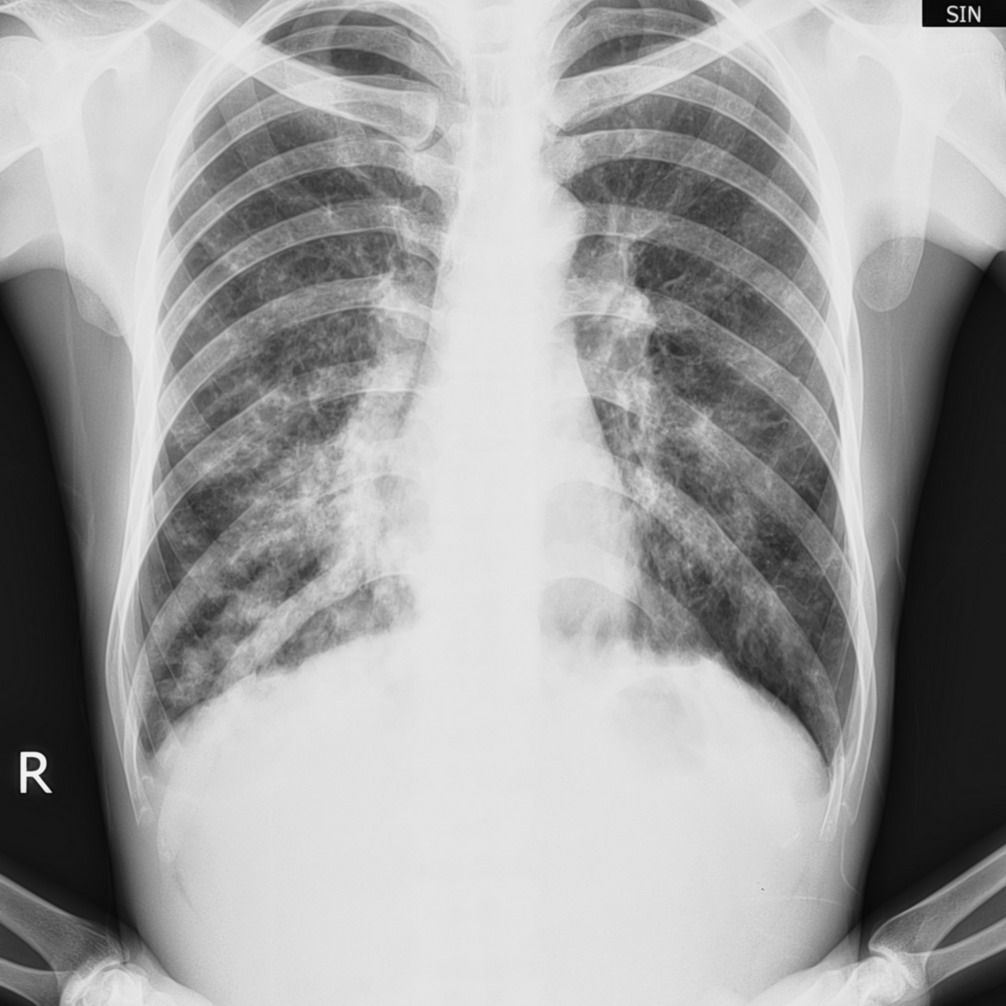

以下是引用眼睛在2008-4-26 18:17:00的发言:[br]两下肺纹理紊乱,可见囊状,斑片状影,以左侧为重,诊断:支扩合并感染. 建议ct